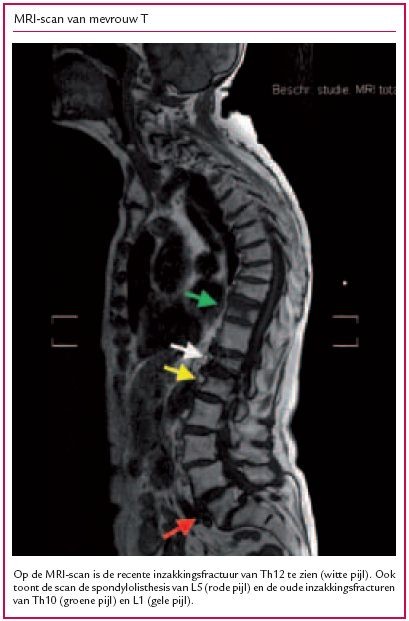

Mevrouw T, 87 jaar, vraagt een visite aan bij haar huisarts vanwege hevige rugpijn die de laatste dagen steeds erger is geworden en toeneemt bij bewegen. Ze kan door de pijn niet meer naar de praktijk komen. Ze is nog erg vitaal, maakt regelmatig uitstapjes met de deeltaxi en bridget fanatiek. Patiënte is bekend met COPD, hypertensie en cataract, en heeft een CVA in de voorgeschiedenis waar ze goed van is hersteld. In haar probleemlijst staat verder dat op een röntgenfoto in 1982 spondylolisthesis van L5 en spondylosis en discopathie van C5-6 zijn gevonden, en dat in 1990 osteoporose is vastgesteld. In 2003 is patiënte internistisch onderzocht in verband met een fractuur van Th10 en een verhoogde BSE. Na uitgebreid onderzoek bleek er alleen sprake te zijn van osteoporose; de internist schreef risedroninezuur 35 mg per week en calciumcarbonaat voor, ‘levenslang te gebruiken’ zoals hij meldde in de brief aan de huisarts. De rugpijn waarvoor patiënte nu belt, zit lager dan in 2003 en paracetamol helpt onvoldoende. Gezien de voorgeschiedenis en de locatie van de pijn vermoedt de huisarts een inzakkingsfractuur op lumbaal niveau. Mevrouw T wil in eerste instantie geen röntgenfoto, omdat ze daarvoor naar het ziekenhuis moet. De huisarts schrijft haar twee weken diclofenac in combinatie met omeprazol voor (bij een recente controle had ze een eGFR van 46 ml/min). Vijf dagen later heeft patiënte echter nog zoveel pijn dat nadere diagnostiek wel bespreekbaar is. Op de röntgenfoto van de lumbale wervelkolom is alleen een oude inzakkingsfractuur van L1 te zien. De pijn wordt vervolgens vrij snel minder. Twee maanden later is er opnieuw een episode met heftige acute rugpijn, laagthoracaal. Op de röntgenfoto, die nu wel meteen gemaakt wordt, is de oude fractuur van Th10 te zien en een nieuwe fractuur op niveau Th12. Aanvankelijk start mevrouw weer met diclofenac, maar vanwege de aanhoudende heftige pijnklachten gaat zij na vijf dagen over op morfine-retardtabletten, tweemaal daags 10 mg. Mevrouw T heeft al jaren twee- tot driemaal per dag wat dunne ontlasting en wil daarom geen laxans gebruiken. Na drie dagen moet de dosis morfine verhoogd worden naar tweemaal daags 20 mg. Dit gaat echter gepaard met misselijkheid. De morfinetabletten worden vervangen door een fentanylpleister van 12 μg/uur, maar ook hiermee blijft patiënte erg misselijk. Ondertussen krijgt patiënte fysiotherapie aan huis, maar die verloopt door de pijn zeer moeizaam. Zij heeft hulp nodig bij ADL-activiteiten die ze voorheen zelfstandig uitvoerde. Ze kan niet meer alleen naar het toilet en niet meer opstaan uit haar stoel. Ten einde raad belt de huisarts vier weken na de start van de nieuwe pijnklachten de orthopedisch chirurg met de vraag of deze nog behandelmogelijkheden ziet. Volgens de chirurg is een vertebroplastiek nog een optie. Om de indicatie daarvoor te bepalen moet het exacte niveau van de fractuur vastgesteld worden, evenals de mate van consolidatie. Als de hiervoor benodigde MRI gemaakt wordt, zijn er twee maanden verstreken sinds het begin van de laatste pijnepisode. Op de MRI is de recente fractuur van Th12 zichtbaar naast de oudere fracturen (zie de afbeelding). De pijnklachten zijn op dat moment dermate afgenomen dat de chirurg in overleg met patiënte afziet van de operatie.